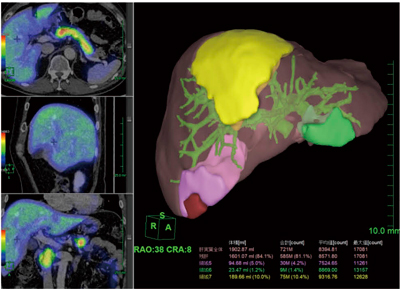

(5) 機能画像(PET・SPECT等)とフュージョンが可能:アシアロシンチグラフィ等とフュージョンさせることで,残肝の機能を評価することができる(図4)。

図4 機能画像(アシアロシンチグラフィ)とのフュージョン